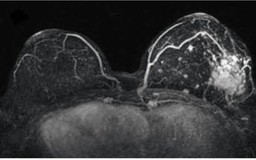

Những nguyên nhân nào gây sưng hạch bạch huyết ở nách?

Hạch bạch huyết nằm ở nhiều vị trí khác nhau trong cơ thể như nách, cổ và bẹn. Riêng ở nách có hơn 20 hạch bạch huyết. Sưng hạch bạch huyết ở vùng nách có thể do nhiều nguyên nhân khác nhau gây ra. Điều quan trọng là cần phải theo dõi sức khỏe chặt chẽ.

Thuốc đích trong điều trị ung thư vú

Kiểm soát nguy cơ 'ung thư gia đình' do đột biến gien